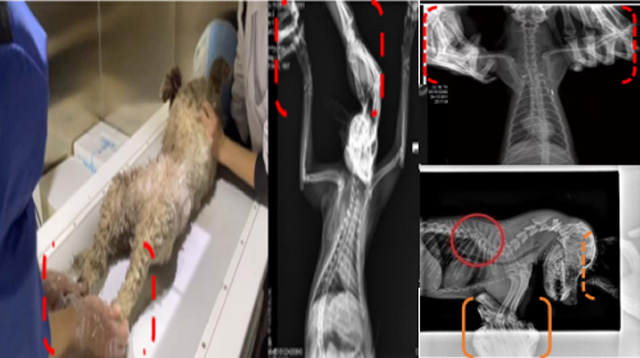

现在宠物医疗设备得到高速发展,现在有越来越多的宠物诊疗机构配置X射线装置如宠物DR。宠物骨折或者有其他疾病不能通过直观看出来的。宠物诊所医生都会使用宠物DR来做辅助检查。但是有时候宠物医生没有加强防护,就在宠物DR室给宠物拍X片做检查。这样也是会受到X射线的辐射。因为X射线上岗是属于职业病危害岗位。长期的辐射会对人体造成一定的危害。宠物医生也需要接受X射线照射的上岗前都必须进行放射工作人员的职业健康体检。体检不合格的话是不能担任放射工作的。未经上岗前职业健康体检的劳动者从事接触职业病危害作业的行为,已经违反了《中华人民共和国职业病防治法》第三十五条规定,依据《中华人民共和国职业病防治法》第七十五条规定,需要进行整改罚款。开展宠物放射诊疗活动,在日常工作中,对本机构的X射线危害的职业病防治,需要知道并做到以下内容: